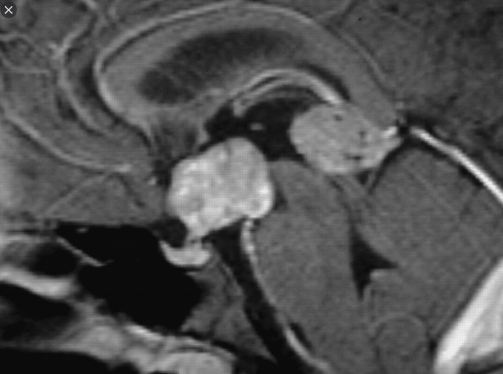

Describe the image.

Coronal contrast T1 reveals a lesion in the right CPA causing mass effect on the adjacent brainstem. There is normal contrast enhancement of the contralateral choroid plexus. There does not appear to be any leptomeningeal enhancement. Axial FLAIR reveals a substantial vasogenic edema in the right brachium pontis and deep cerebellar nuclei. The left flocculus is normal.